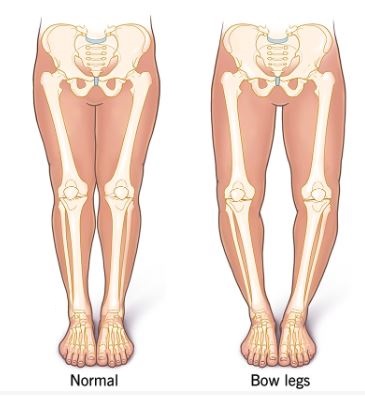

Bow legs (genu varum) is a condition where one or both of your child’s legs curve outward at the knees. This creates a wider space than normal between the knees and lower legs. When your child stands with his or her feet and ankles together, the knees stay wide apart. Your child’s legs may look like a bow, especially when they walk.

The main sign of bowed legs is the appearance of your child’s legs. Their knees won’t touch when they stand with their feet and ankles together. The bowing is most obvious when they’re walking. Sometimes children may walk with their toes pointed inward (pigeon toes or intoeing).